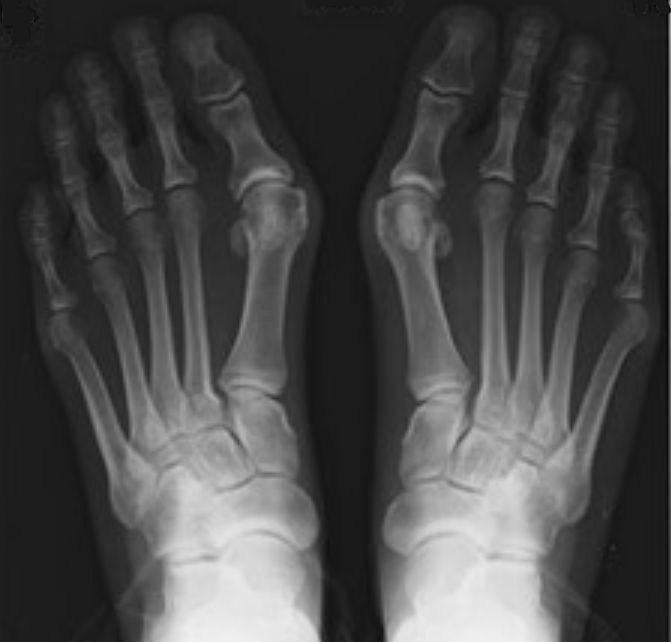

Genetika: Jedním z hlavních faktorů je dědičnost. Pokud někdo z vaší rodiny trpí vbočeným palcem, je pravděpodobné, že i vy budete mít sklony k této deformitě. Pokud se podíváme na řadu snímků chodidel, můžeme si povšimnout, že snímky s halluxem mají ještě k tomu kratší kost v zánártí – oproti prstu ukazováku. Tedy kloub palce je postavený blíže k patě (ve srovnání s vedlejším prstem). A celkové rozložení váhy je méně vyvážené a tím vzniká tento nešvar. O tomto se téměř nikde nedočtete, ale při dlouhodobějším pozorování zjistíte, že to svoji logiku má.

Na obrázku níže vidíme, jak základní kloub palce je o něco blíže k patě než další prsty (jeho kost v nártu je kratší, než kosti dalších prstů). A na pravé noze je to při porovnání s ukazovákem ještě větší rozdíl a proto bychom mohli hledat souvislost s kratší kostí a větším odchýlením palce od ukazováku v místě kloubu.